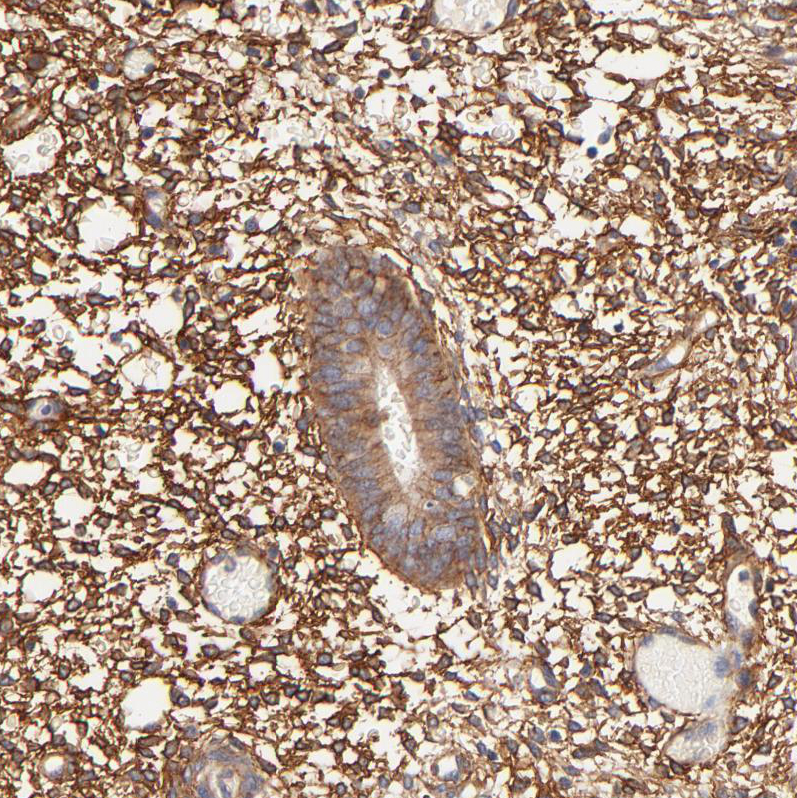

Receptor protein tyrosine kinases transduce extracellular signals across the cell membrane. A subgroup of these kinases lack detectable catalytic tyrosine kinase activity but retain roles in signal transduction. The protein encoded by this gene an intracellular domain with tyrosine kinase homology and may function as a cell adhesion molecule. This gene is thought to be expressed in colon carcinomas but not in normal colon, and therefore may be a marker for or may be involved in tumor progression. Four transcript variants encoding four different isoforms have been found for this gene.

PTK7 serves as a context-dependent signalling switch for the Wnt pathways (particularly in planar cell polarity related functions such as convergent extension and neural crest cell migration) and appears to have similar functions for plexin and Flt-1 pathways. PTK7 was identified to be highly expressed in colon cancer by Saha et al. using serial analysis of gene expression (LongSAGE). Pfizer is targeting PTK7 for cancer by generating an antibody-drug conjugate against the PTK7 receptor.